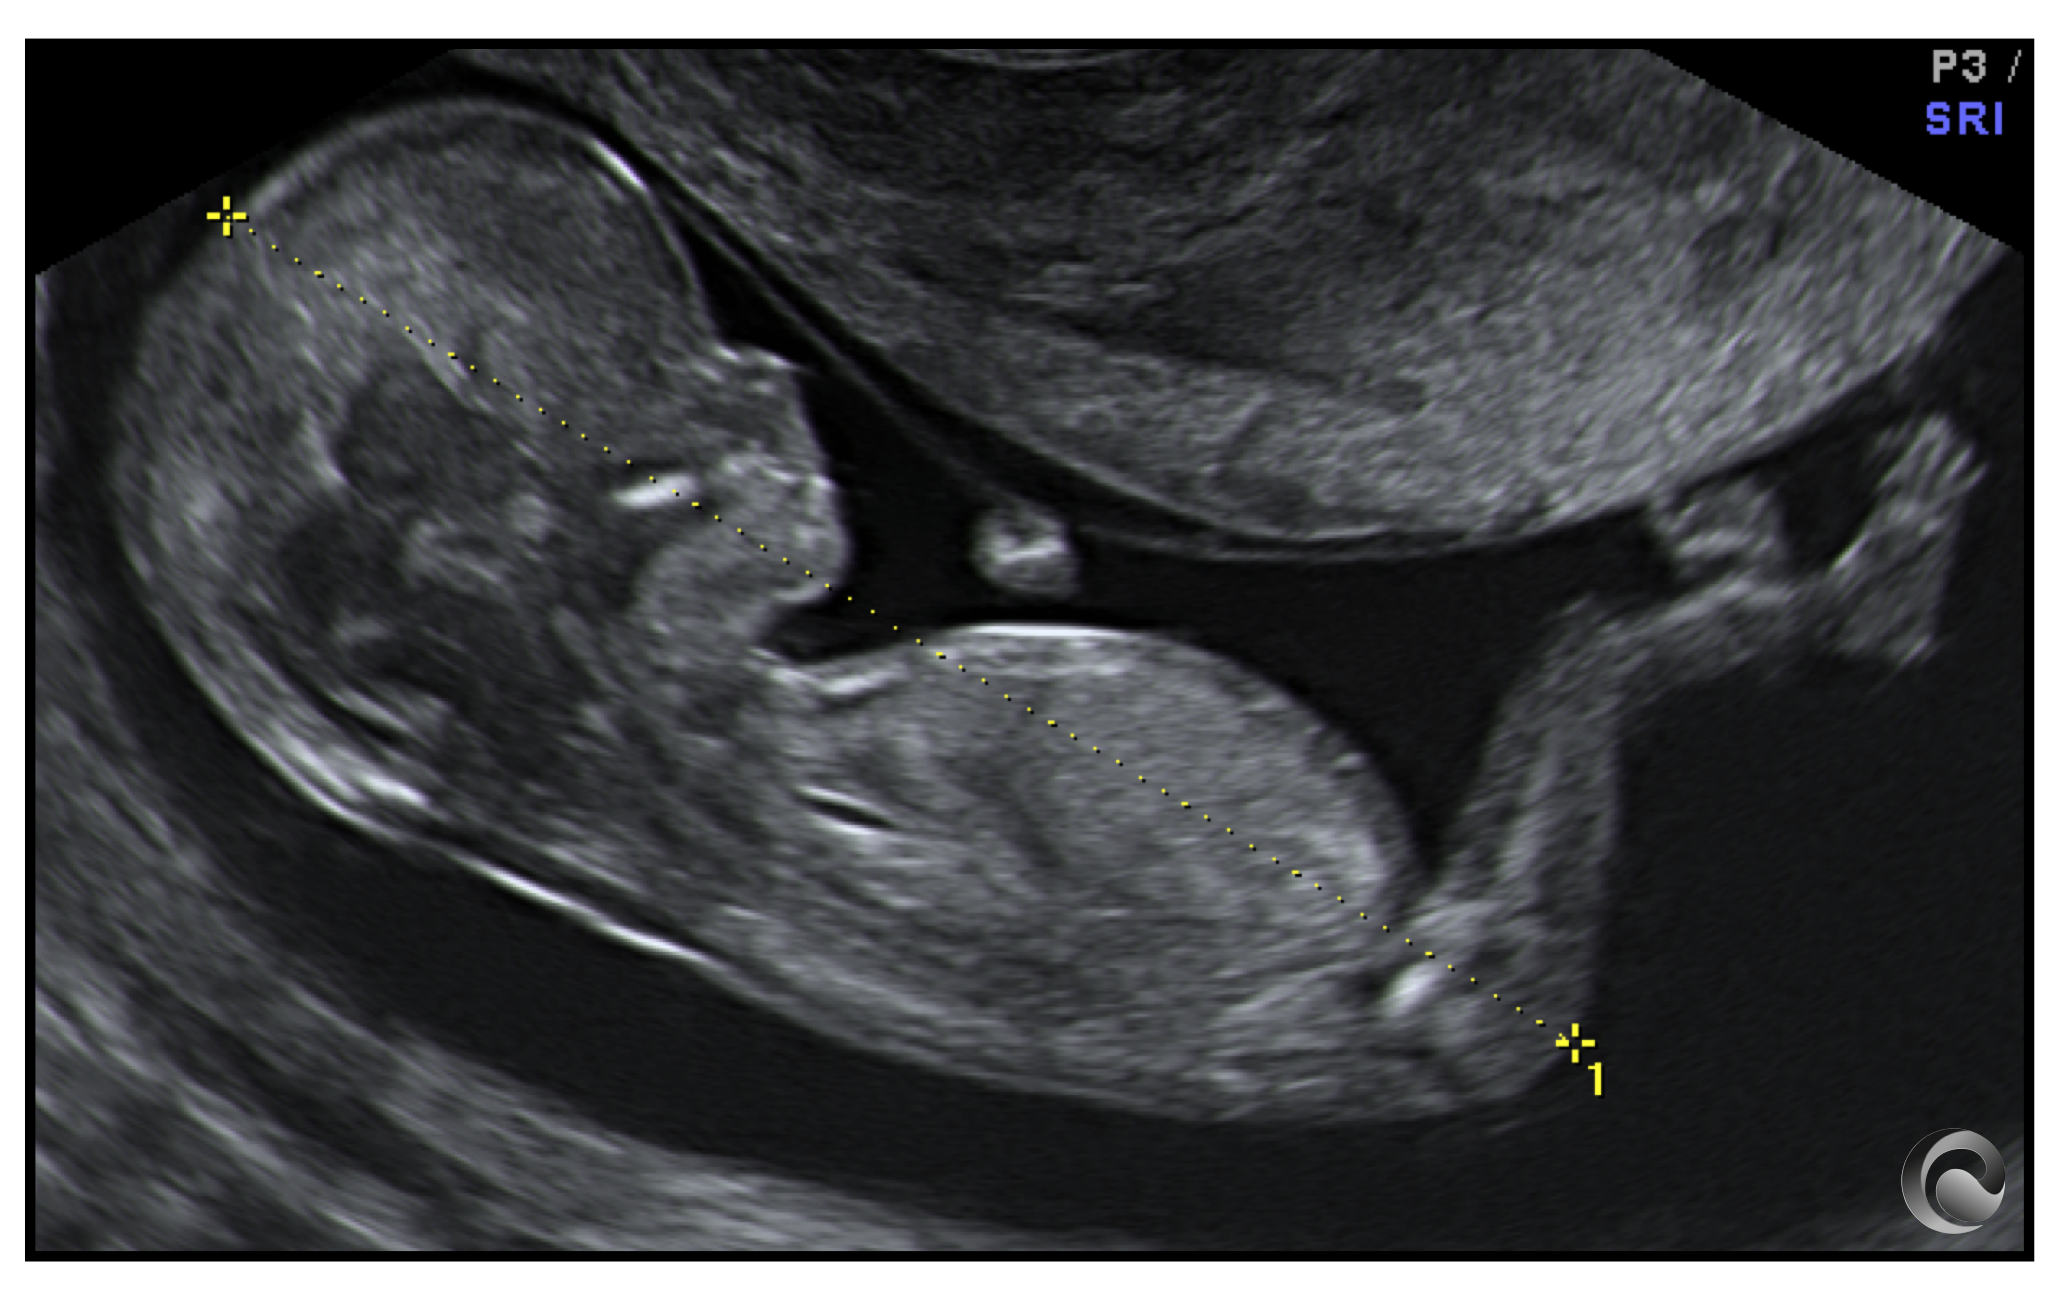

Product Item: Screening embarazo clearance segundo trimestre

Screening embarazo clearance segundo trimestre